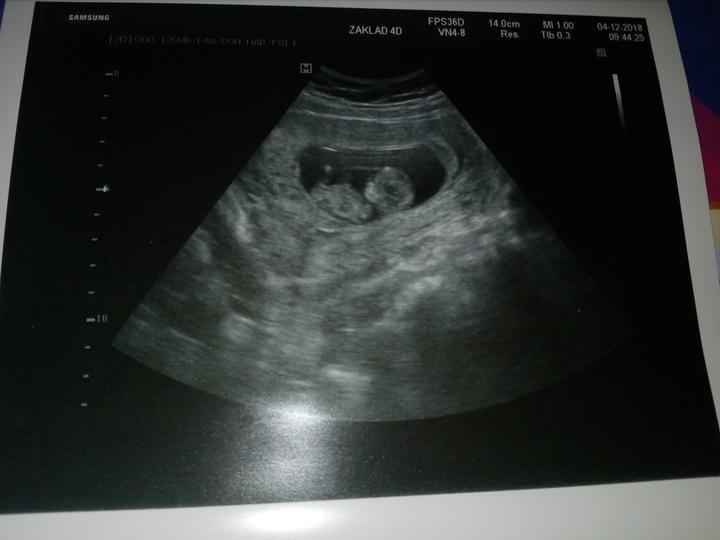

To nase dite dela "Zagorku". Porad se na screeningu vrtel a otacel na bok, byl zaboreny az dole. Ale asi nam hrozi prstickem😂vsimnete si toho?😊Jinak odpovidame 12+4 a termin porodu nam nezmenil. Rikali, ze pokud dnes nikdo volat nebude tak jsou vysledky krve dobre a nikdo nevolal takze super, spadl mi kamen ze srdce. Akorat mam nejake varixy tak mozna budu muset po porodu pouzivat heparin, ale nic vazneho to neni, ale zkoumal to podrobne.